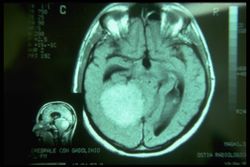

Non da meno è il nostro paziente 'Bruxer' che precedentemente diagnosticato come TMD seguendo lo RDC è risultato essere affetto da 'Cavernosa Pineale'. Anche in questo caso, abbiamo rimarcato che non si tratta di preparazione e professionalità del medico nel seguire linee guida specifiche e fare diagnosi nel contesto specialistico bensì di alcuni elementi che ad un primo approccio sfuggono all'attenzione del medico. In primis va un pò ridimensionato il concetto troppo vincolante di 'variabile dipendente' e cioè referto positivo di immagini della AT, uguale, Disordini Temporomandibolari (TMDs). Anche se con un alta percentuale di casi ciò potrebbe verificarsi dovremmo sempre tenere a mente che una diagnosi troppo superficiale ed automatica potrebbe mettere a rischio la vita del paziente come proprio sta succedendo al nostro 'Bruxer'

E' proprio il caso del nostro 'Balancer' che dopo anni di pellegrinaggio odontoiatrico per correggere postura e occlusione si è scoperto essere affetto da voluminoso 'Meningioma'. Purtroppo per questo paziente siamo arrivati tardi. Teniamo conto, come detto ma è bene ribadirlo, che un menigioma necessita di decenni per giungere ad un diametro di 8 cm. La cosa più dolorosa in tutto ciò che avevamo già ai tempi in cui fu fatta la diagnosi definitiva i mezzi e le metodologie elettrofisiologiche trigeminali per fare immediatamente diagnosi di danno organico trigeminale.